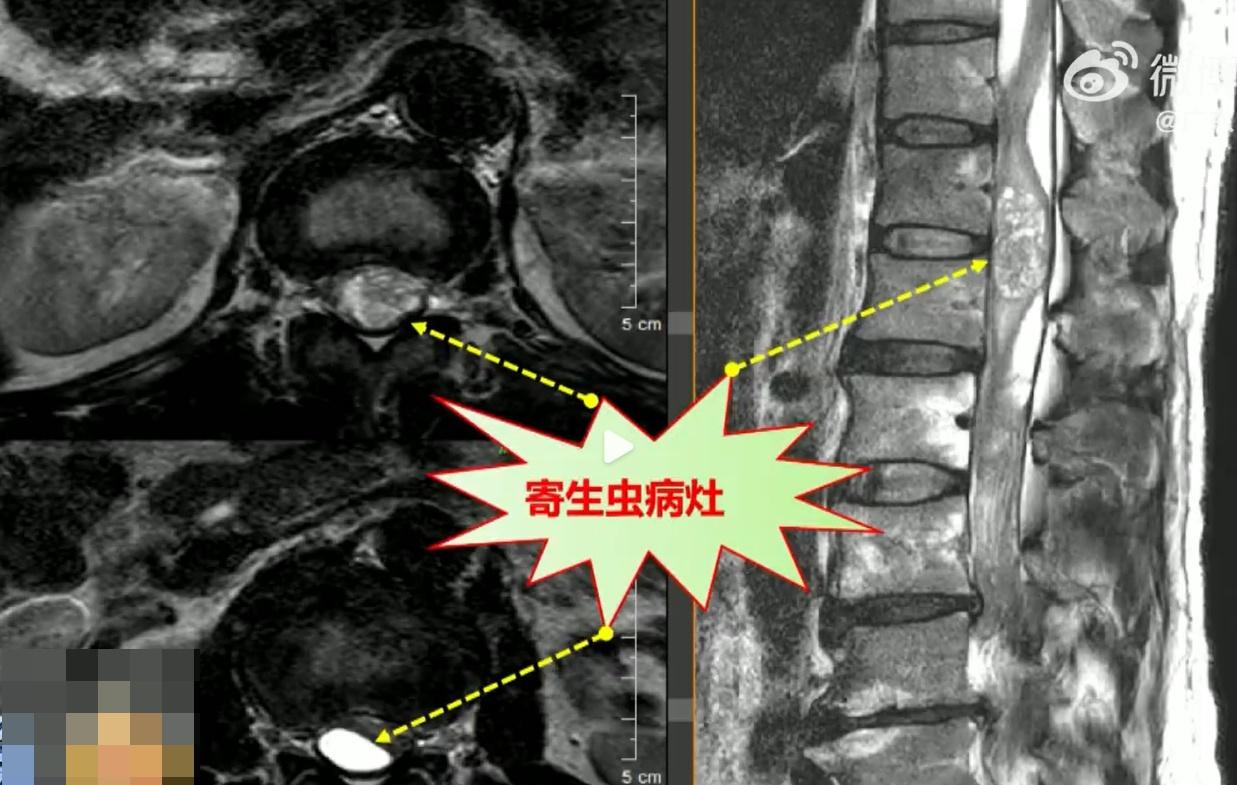

綜合報道,廣州55歲郭先生因為體質容易「上火」,15年前聽信老人家的偏方,多次生吞蛇膽、飲蛇膽酒,希望能終止經常潰瘍的癥狀。結果2年前,他突發頭暈、惡心、行走不穩的癥狀,多番求醫,雖經治療部分緩解,直至今年2月病情再次惡化,郭先生在南方醫科大學第三附屬醫院求醫時,醫生初步推斷他的怪病很可能是非常罕見的「脊髓內寄生蟲感染」,經化驗標本後,確定他是感染「曼氏裂頭絛蟲」。

有寄生蟲長度達約6厘米 醫生:相當驚人

負責手術的南方三院脊柱外科副主任黃敏軍表示:「切下的標本全是寄生蟲,患者的脊髓全都被寄生蟲的排泄物感染,寄生蟲不斷繁殖擴大,有的長度甚至達約6厘米,相當驚人。」由於郭先生的寄生蟲與脊髓神經黏連,醫院共耗時4小時才將大部分病灶清除。此外,由於殘存的病灶非常廣泛,為防止寄生蟲再度滋生,郭先生需要再次接受驅蟲治療。他在接受治療期間表示害怕,坦言:「以後真的不敢吃那些東西了。」醫生也特別呼籲,青蛙肉、蛇膽、蛇血、蛇肉等較容易有寄生蟲,大眾應盡量避免食用,以免引發類似的感染病例。